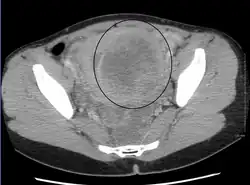

-

A very large (9 cm) fibroid of the uterus which is causing pelvic congestion syndrome as seen on CT -

A relatively large submucosal leiomyoma; it fills out the major part of the endometrial cavity. -